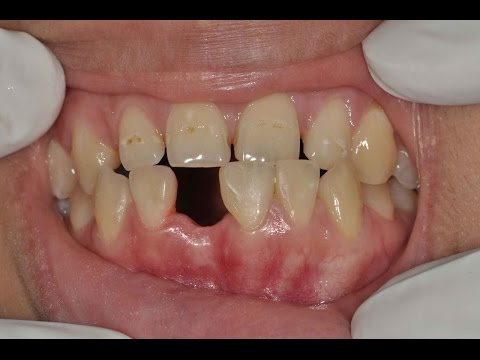

Hiányzó fogak pótlása, műgyökér beültetéssel